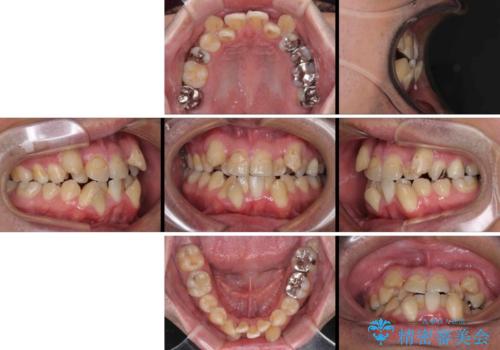

- 上下の八重歯やデコボコを気にして来院された患者様です。

上下ともに八重歯が顕著であったので、上下左右第一小臼歯4本を抜歯し、ワイヤー装置にて矯正治療を行うこととしました。

デコボコが強いことが原因で歯間部に汚れが溜まりやすい状態でしたが、矯正前にできる限り汚れが少なくなるようにブラッシングなどの指導を行い、口腔状態が改善された後にワイヤー装置を装着することとしました。

結婚式をきっかけに矯正治療を決意したとのことでしたが、挙式までの期間があまりにも短かったために、結婚式後に治療を開始することとなりました。